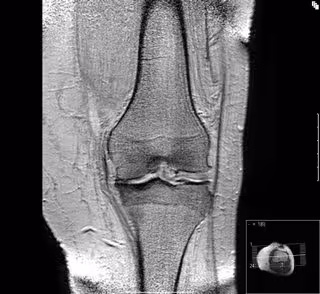

Artrosis de rodilla